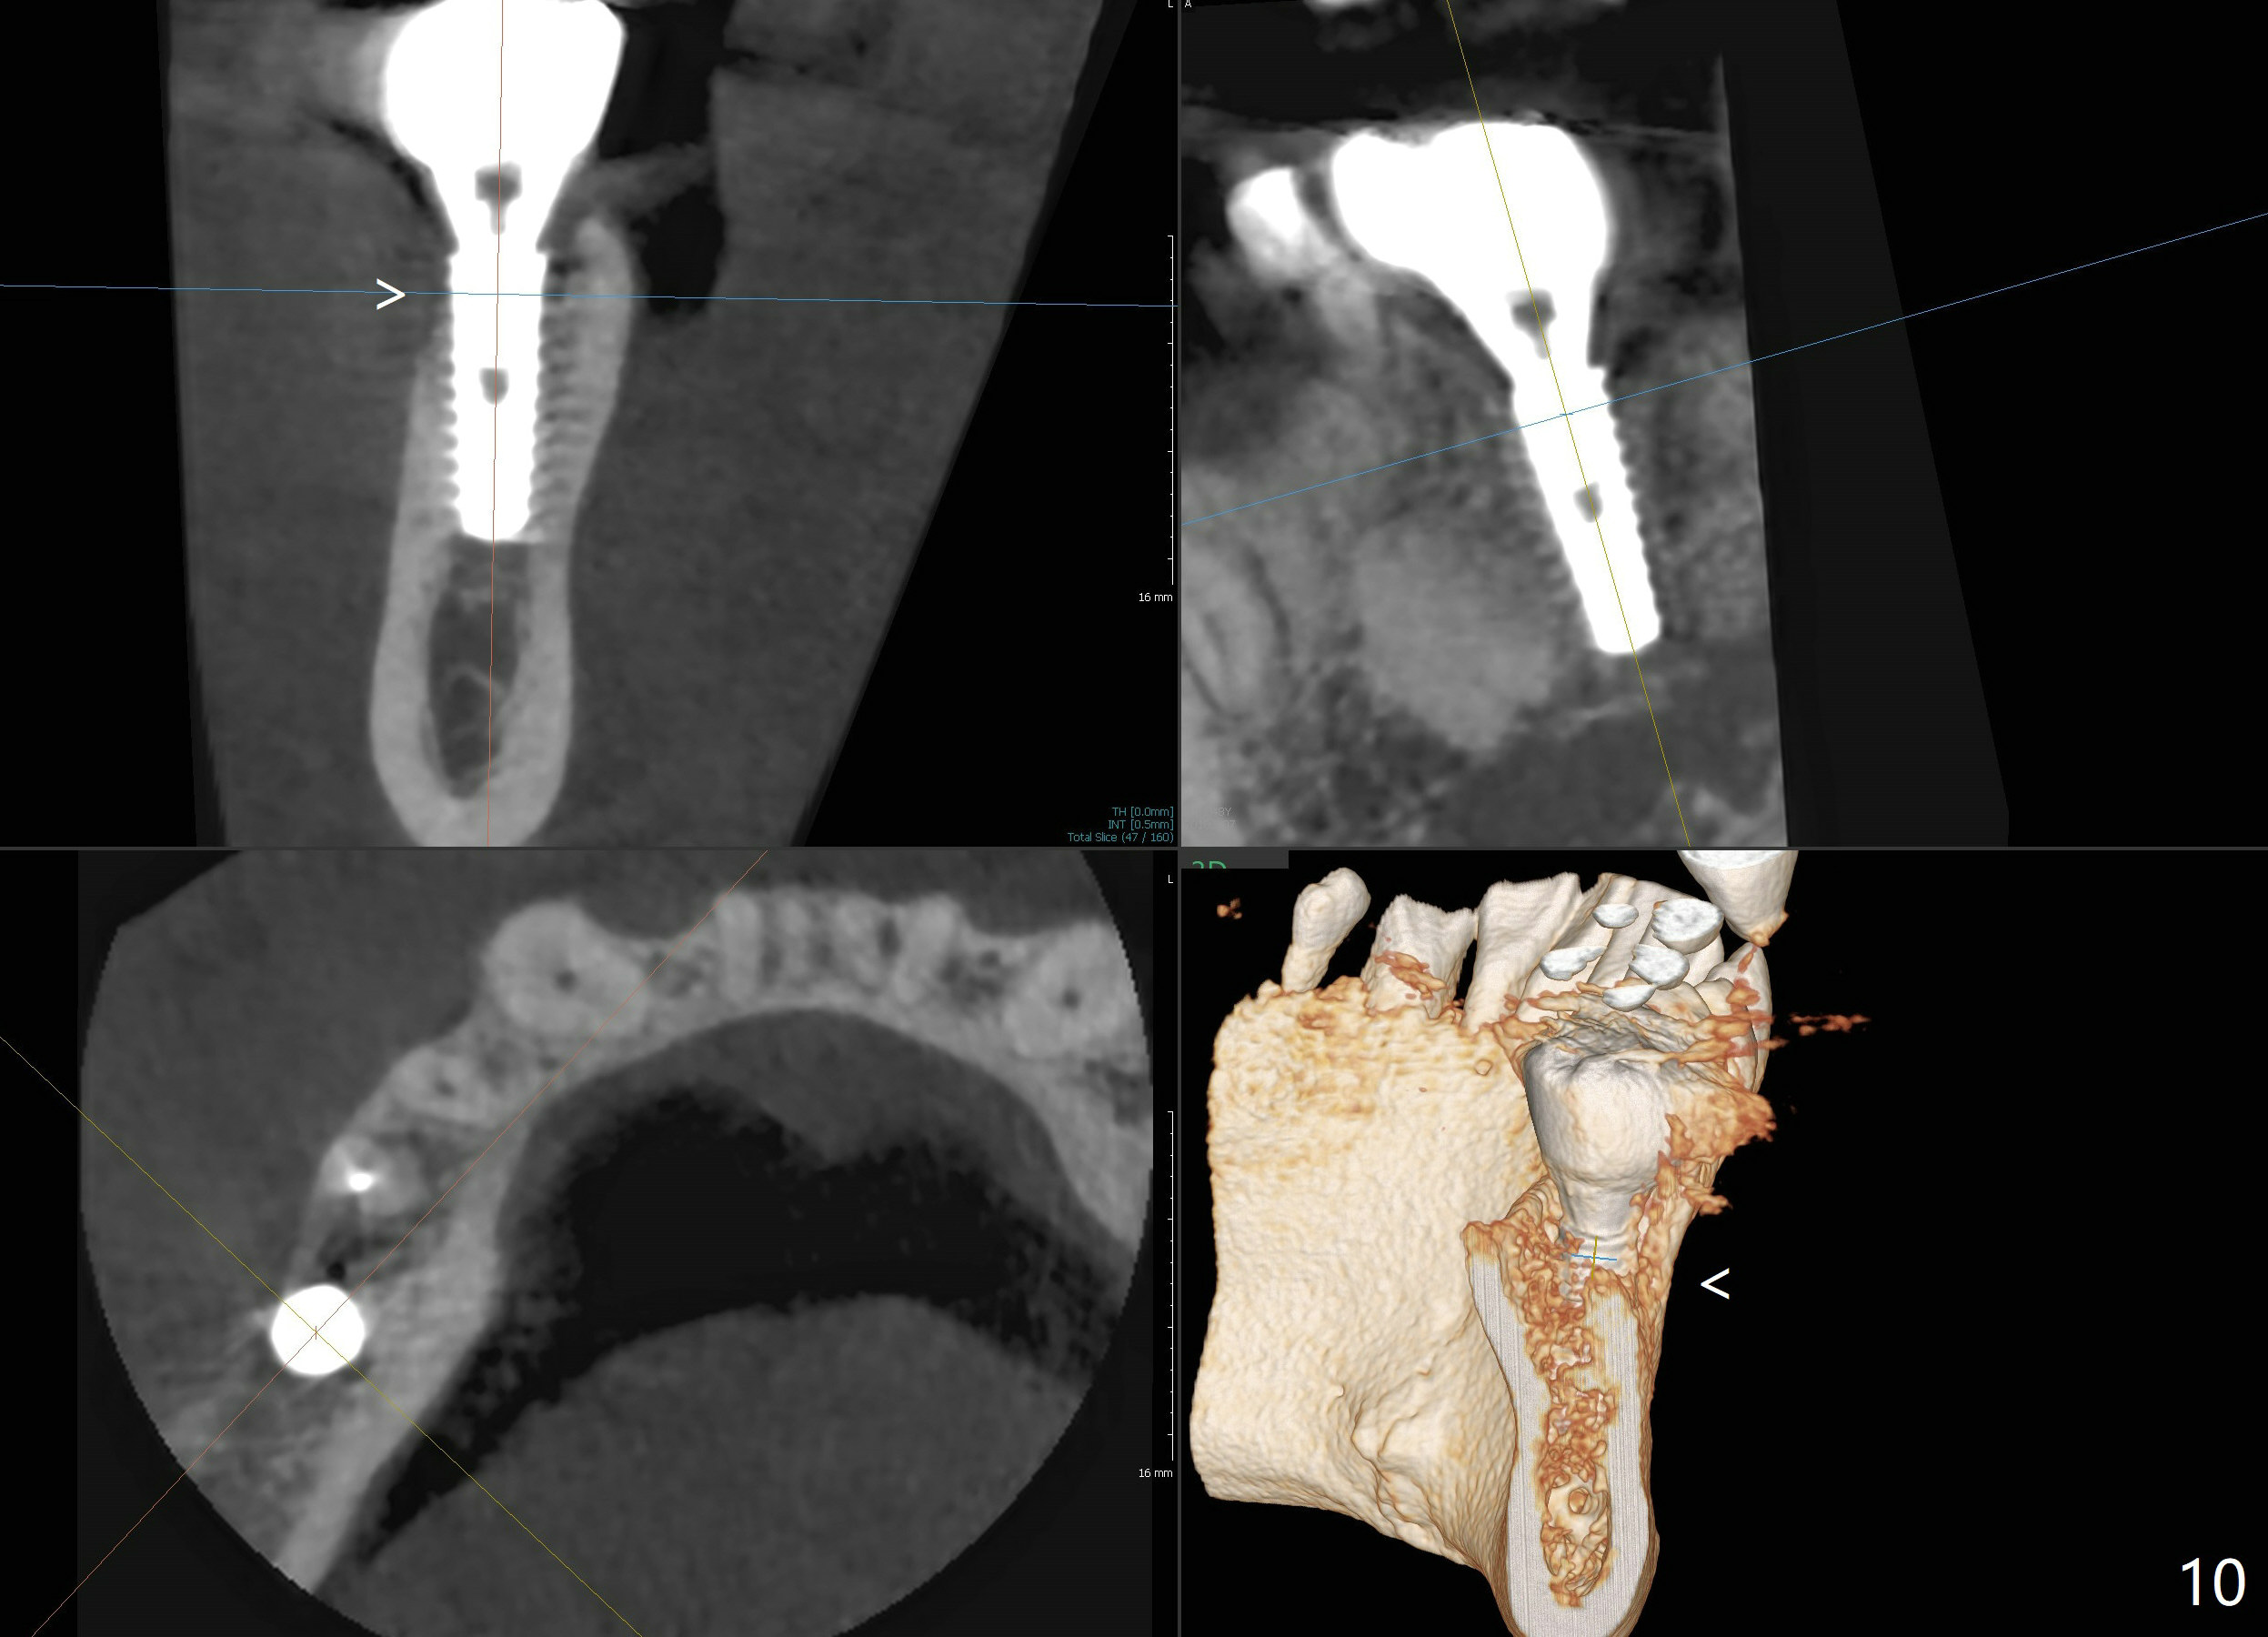

Bone graft seems to sink down and becomes denser 3 months postop (Fig.6 arrow). The bone continues being denser 5 months postop (Fig.7). There is periapical radiolucency of the tooth #29 (^). RCT is done (Fig.8). The pain persists 2 weeks postop (Fig.9,10). There is no missing canal (Fig.9). The apex is close to the implant (Fig.9 *). Apicoectomy will be performed if needed. It appears that the implant is also placed buccal (Fig.10 <) and/or the implant too large for the site. Therefore there should be a 2-3 mm buccal gap before and after implant placement. Separation and reflection of the buccal flap allows better visibility. The pain persists 1 month post RCT and 6 months post implant placement. RCT retreatment is initiated (Fig.11,12) with placement of Calcium Hydroxide paste after redebridement with 30/.04 rotary file at 23.5 mm (.5 mm longer than the earlier RCT, Fig.13). RCT retreatment finishes with apparent transportation and extrusion in 4 weeks (Fig.14,15), followed by apicoetomy (Fig.16,17) (20 days later)). Discomfort remains 2.5 months postop (Fig.18). Keep watching.